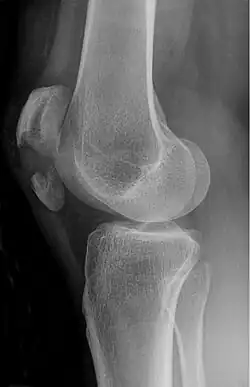

The patella can break in various ways depending on the way it is injured, and into two or more pieces.[1] Types include transverse, the most common, with one fracture line;[5] marginal; osteochondral; and the rare vertical type, or stellate, where a direct compression force gives rise to a comminuted pattern.[5][7] Patella fractures can be further classified as displaced, where the broken ends of bone do not line up correctly and separate by more than 2mm, or undisplaced and stable where pieces of bone remain in contact with each other.[1][7] If fragments of patella bone stick out from the skin it is known as an open patella fracture, and closed if the overlying skin is intact.[1]

Transverse fracture of patella